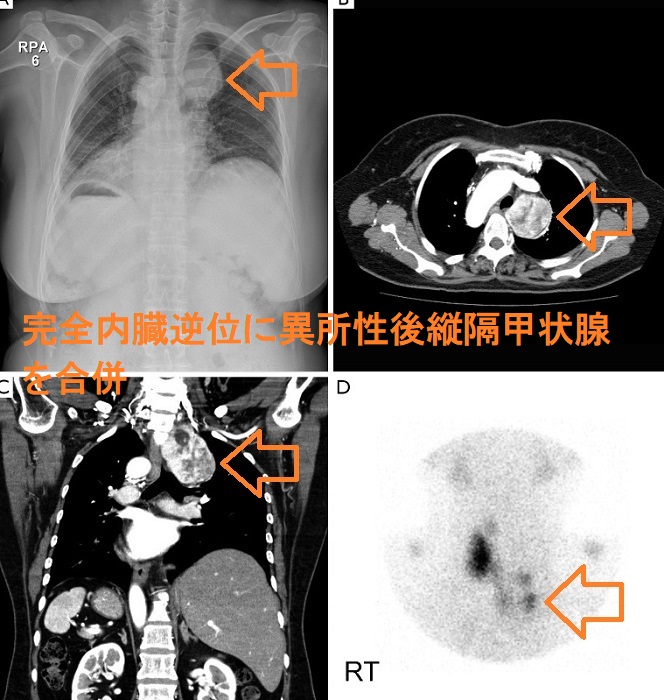

異所性後縦隔甲状腺は非常に稀で、全縦隔腫瘍の1%未満です。異所性後縦隔甲状腺は、大きくなって心血管系を圧迫するまで無症状、発見時には転移性甲状腺癌との鑑別が必要になります。完全内臓逆位に異所性後縦隔甲状腺を合併した62歳女性の報告があります。[J Thorac Dis. 2014 May;6(5):E39-42.]

また、甲状腺濾胞癌で甲状腺全摘手術した後、縦隔内甲状腺腫が見つかった完全内臓逆位の55歳女性の報告があります。[Q J Nucl Med. 1995 Jun;39(2):116-8.]